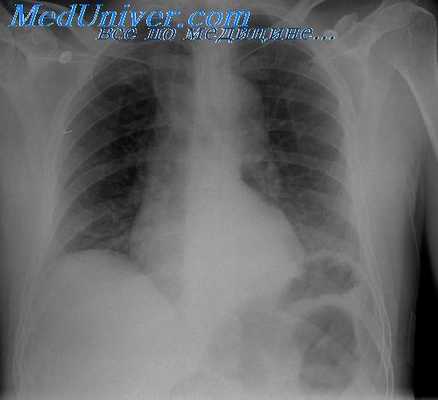

При портальной гипертензии наблюдается варикозное расширение вен пищевода и желудка, которое может осложниться кровотечением. Для оценки локализации и степени выраженности варикозного расширения вен применяют рентгенологическое исследование пищевода и желудка с суль-